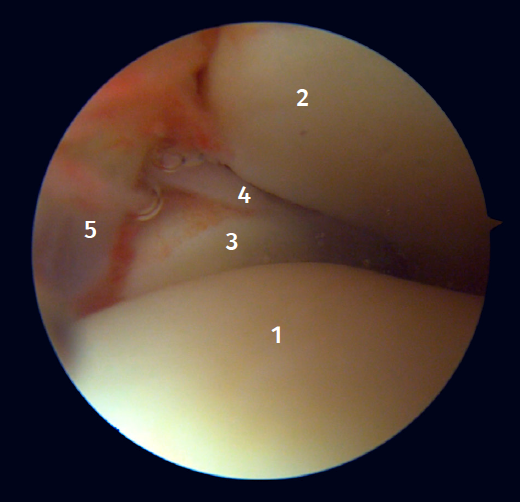

Twenty percent of the ATFL is intra-articular(7). On adopting an anteromedial access of the ankle, directing the arthroscope laterally, we can see the distal fibers of the ATFL with their oblique distribution and their continuation with the anterior talofibular ligament (Figure 2). If we move into the tibiotalar joint, we see the distal tibiofibular joint with the syndesmotic recess occupied by synovial tissue (Figure 3).

Figure 2. Anterolateral arthroscopic view of the right ankle. 1: talar dome; 2: anterior aspect of the tibia; 3: fibula; 4: distal fibers of the anterior tibiofibular ligament; 5: anterior talofibular ligament.

Figure 3. Anterolateral arthroscopic view of a right ankle on entering the tibiotalar zone. 1: talar dome; 2: articular aspect of the tibia; 3: fibula; 4: distal tibiofibular joint; 5: distal fibers of the anterior tibiofibular ligament.